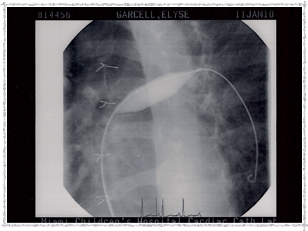

Second Catheterization — Dr. Danyal Khan

In 2010, Elyse underwent her second catheterization procedure, overseen by Dr. Danyal Khan at Miami Children's Hospital. The procedure focused on her pulmonary arteries, and these images show the before and after.

2010 - Left Pulmonary Artery Before

Left Pulmonary Artery — Before

2010 - Before Procedure

Before the procedure

2010 - Left Pulmonary Artery After

Left Pulmonary Artery — After

2010 - Pulmonary Artery Ballooned

Pulmonary Artery ballooned